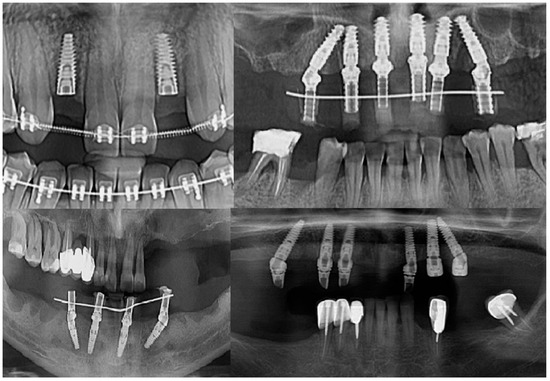

Intraoperatively, the dental implants were screwed into the alveolar bone according to the manufacturers’ indications, being applied over the dental implant with either a covering screw or healing abutment or multiunit abutment (Figure 1). The postoperative wound was sutured with Dafilon™ 4/0 suture thread (BBraun Hessen, Germany BBraun, Spangenberg, Germany) and Dafilon™ 5/0 suture thread (BBraun Hessen, Germany BBraun, Spangenberg, Germany).

Figure 1.

Radiological images presenting different clinical cases included in the study.

A total of 213 patients were selected for the study (Figure 1), and dental implants were inserted in these participants; 78 patients were male and 135 patients were female (Figure 4).